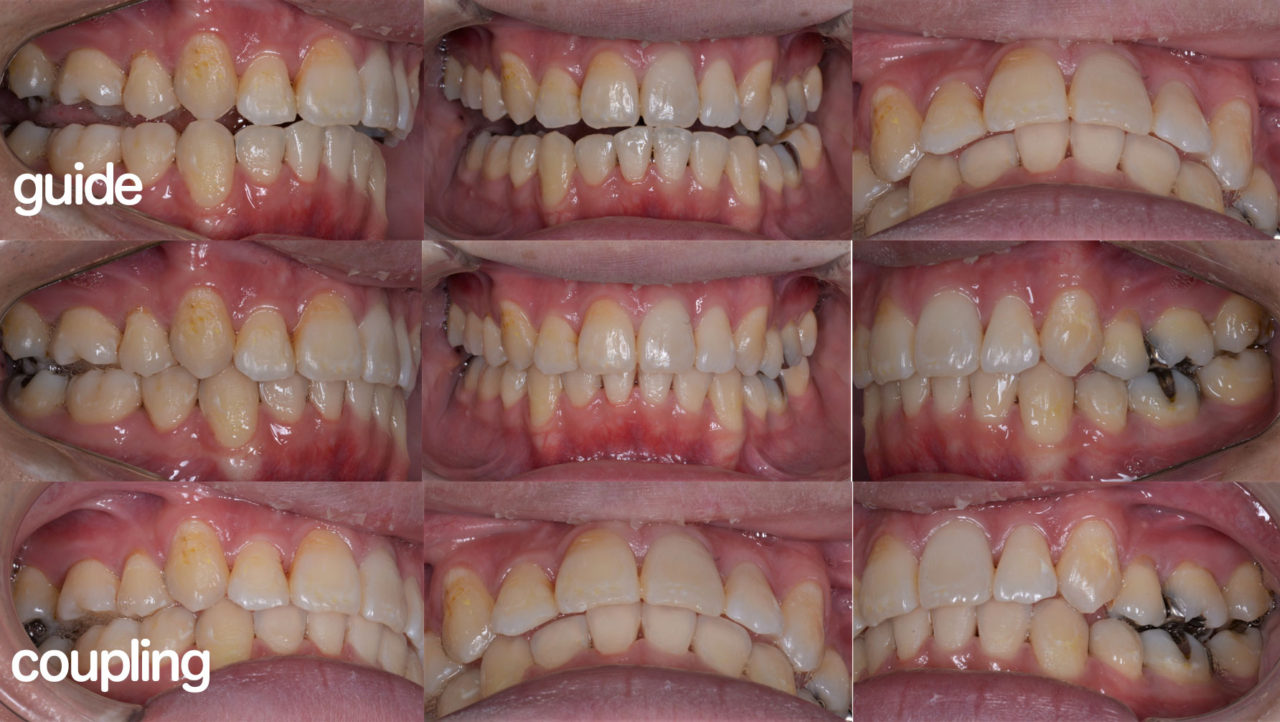

Before

After

| 診断 | 両側アングル1級、上顎前突をを伴う叢生 |

| 矯正方法 | 矯正用アンカーを用い、抜歯を伴うマルチブラケット |

| 矯正期間 | 21か月 |

| 備考 | 左上中切歯の根尖性歯周炎で来院されました。根っこの先に過剰歯があり、左上中切歯の神経は死んでいました。根管治療後、歯列不正を改善のために矯正治療を提案しました。小臼歯4本抜歯を伴うものですが、噛み合わせが良くなるだけでなく、口元もかなりすっきりし、審美を得られる可能性があることを説明をしたところ、快く了承をしていただけました。失活歯で予後不良の左下第2大臼歯も抜歯し、親知らずを利用しました。すべての治療期間は23か月かかりましたが、今後の人生が楽しみになる顔貌の良化を遂げたと考えます。ご本人にも非常に喜んでいただけました。 |